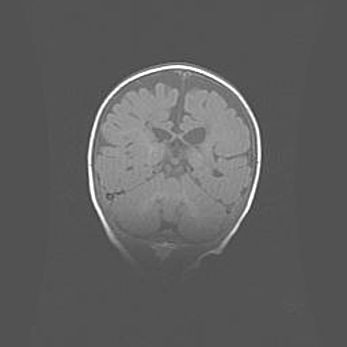

Открытая гидроцефалия.

Возраст: 6 месяцев 15 дней

Вес: 6200 г

Пол: женский

Окружность головы: 41 см

Срок гестации: 38 недель

Гидроцефалия головного мозга у новорожденных – это скопление избыточного количества цереброспинальной жидкости в головном мозге. Ее избыточное скопление в мозге приводит к патологическому расширению желудочков мозга (четырех полостей, расположенных в глубине белого вещества мозга, заполненных цереброспинальной жидкостью и связанных узкими проходами).

Открытый тип гидроцефалии (сообщающаяся) наблюдается тогда, когда нарушен механизм всасывания ликвора в системный кровоток. При этом типе причиной заболевания чаще всего является перенесенные ранее инфекции (например: менингит),  либо же наличие крови в субарахноидальном пространстве.